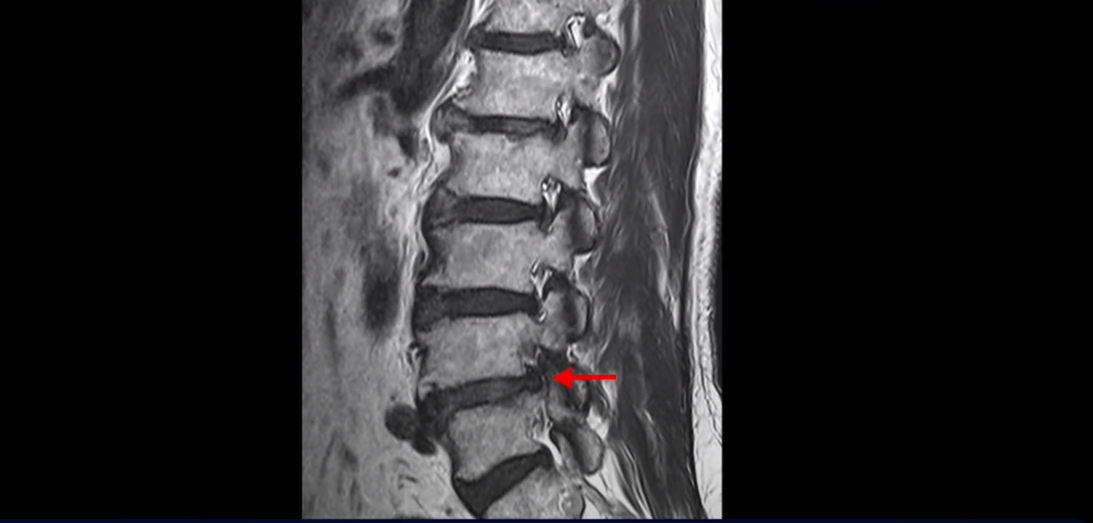

이분 MRI를 보면 척추의 여러 마디가 퇴행이 진행되어 안 좋습니다.

특히 4번 5번 마디가 제일 안 좋은데 보시다시피, 하얗게 보여야 될 신경이 거의 안 보일 정도로 척추관이 좁아져 있습니다.

이분은 허리도 아프지만 왼쪽 엉덩이와 다리가 너무 심하게 저리고 아팠는데 역시나 왼쪽 신경 가지가 빠져나가는 구멍이 막혀 있어서 매우 어둡게 보입니다.

이분은 다리가 너무 아파 걷기 어려워 지팡이를 짚고 모커리에 내원하셨는데요. 어떻게 이런 환자분들을 수술 없이 치료해서 잘 걷게 만들고 심지어는 지팡이 없이 걷게 만들 수 있을까요? 또 어떻게 굽어진 허리가 펴질까요? 지금부터 설명해드립니다.